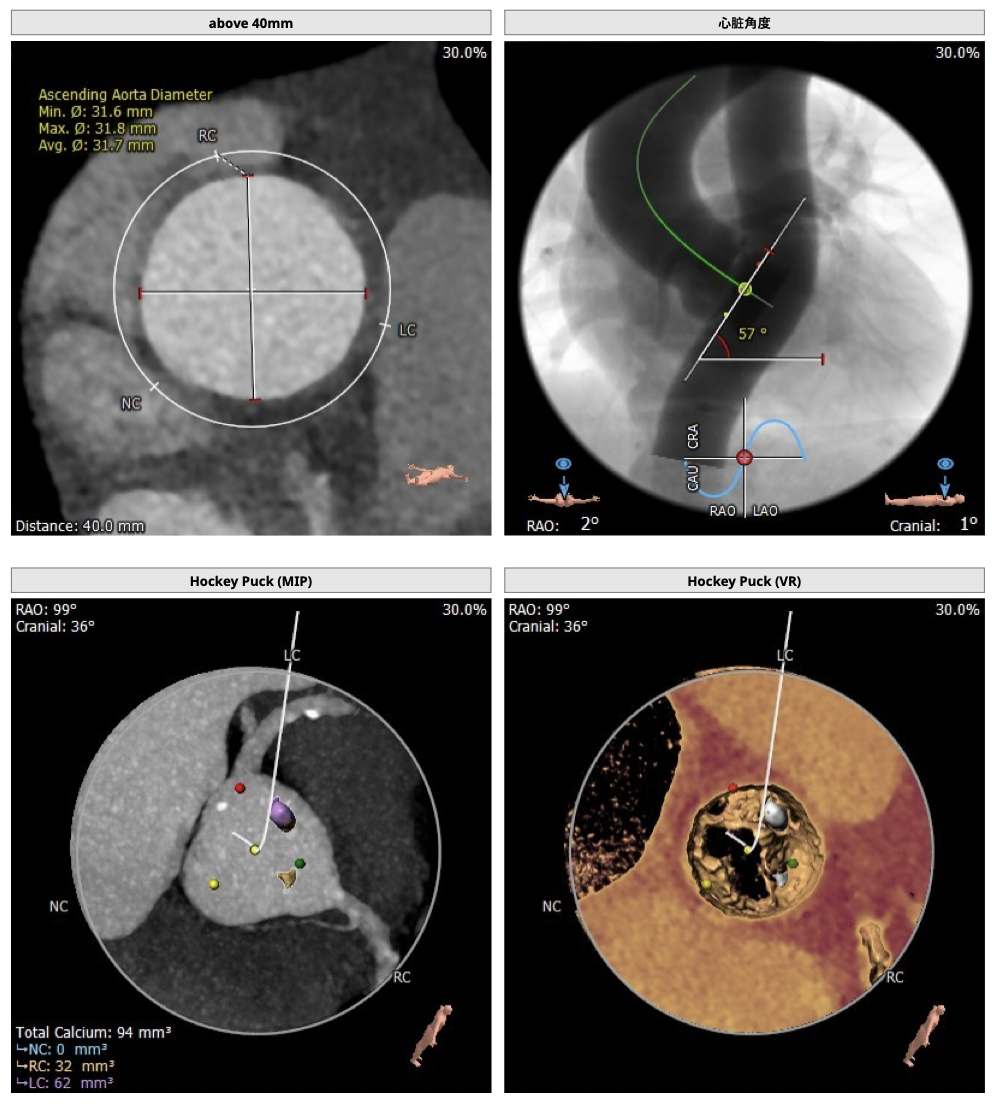

主动脉CT

难点分析:

*患者为TYPE1型二叶瓣,左右融合,重度钙化,融合脊难以推开,瓣膜释放后具有一定瓣周漏风险;

*心脏角度为57°,横位心,输送器过瓣难度增加,瓣膜植入同轴性差,瓣膜释放更易移位,增加了操作的难度;